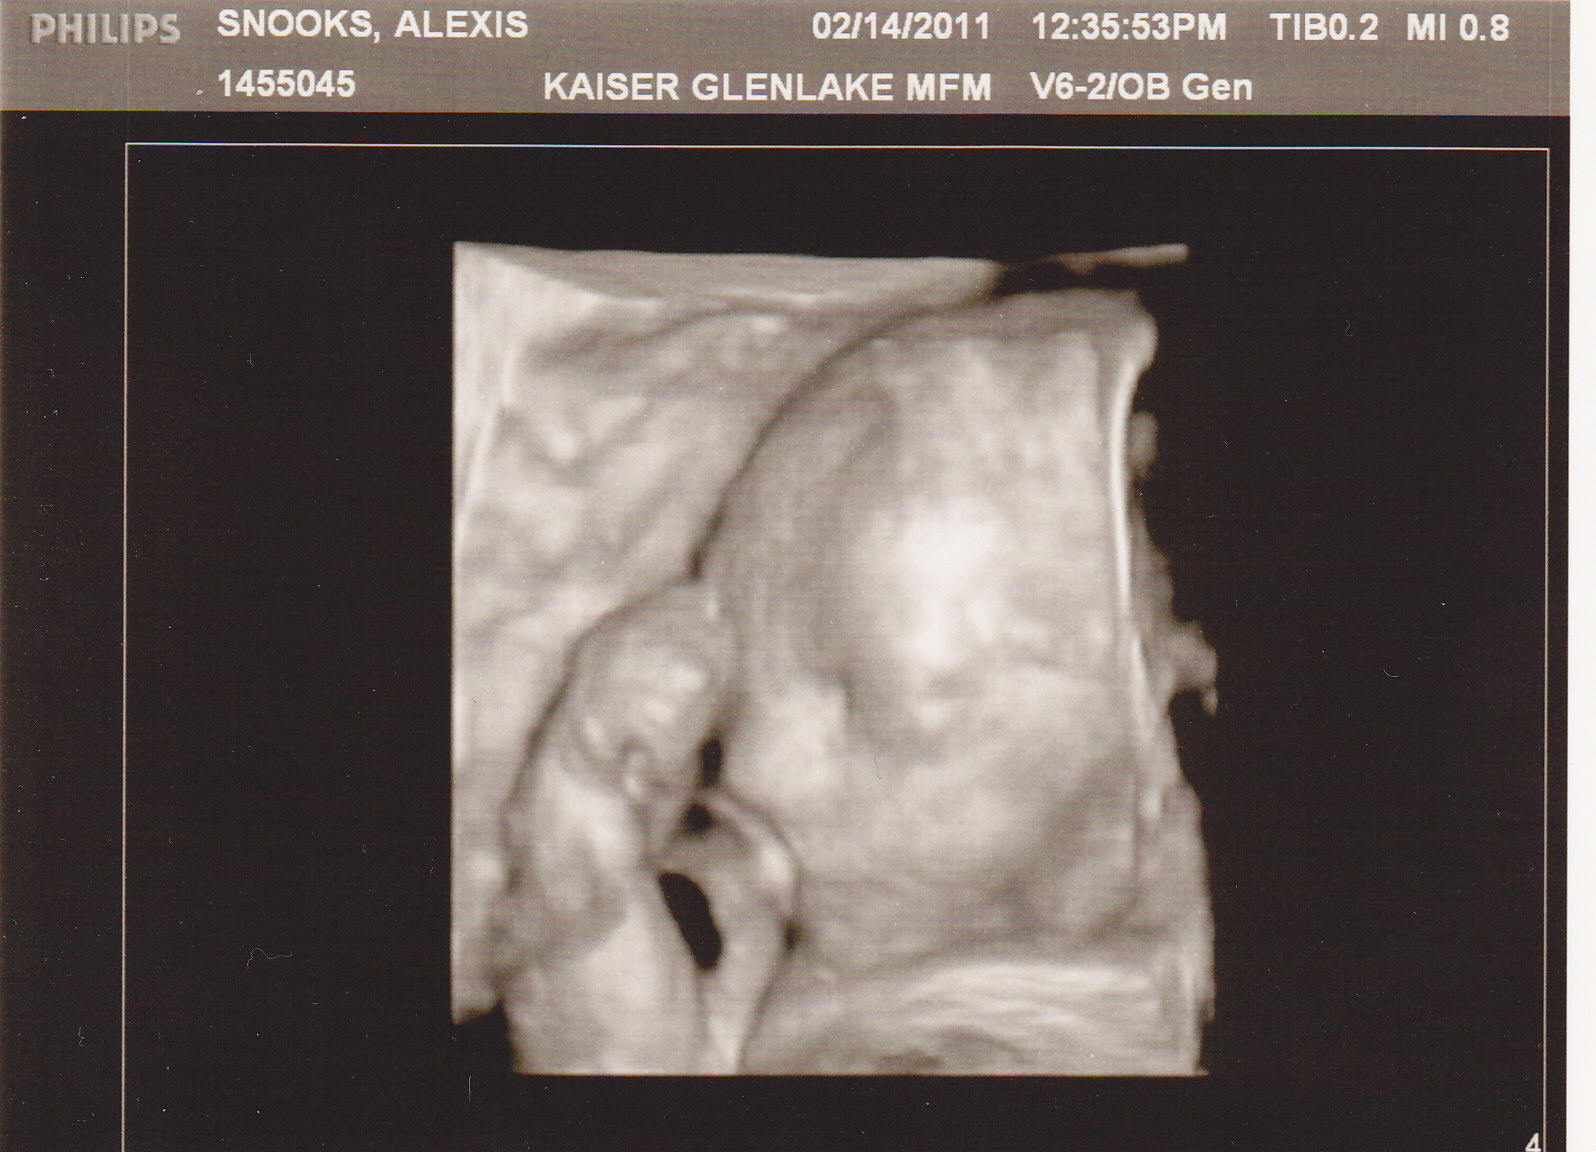

One surprise at this ultrasound was getting to see Logan in 3D :). The nurse secretly switched the ultrasound probes and all of a sudden, I was watching my little man's face! It was the most precious thing I've ever seen :). And while we were watching him, he smiled!!!! Ahhhhhh... he melted his mommy's heart! :) Even though we couldn't get a 'great' picture of his entire face, she still printed 2 pictures for us and they're amazing. I'm even more excited to meet him now :). He is the perfect mix of his mom and dad :).

Also, here are the 3D pictures of him :).

The second one is my favorite :). He has the cutest little face! I could look at it all day :). Anyway, I hope this was informative for you and fairly easy to understand. Please pray for his aortic valve to expand like it needs to so that the blood flow will be even. Also, please pray that he will continue to grow and thrive in his momma's tummy :). Thank you for stopping by to check on us. I'll try to keep you updated on any new developments :).